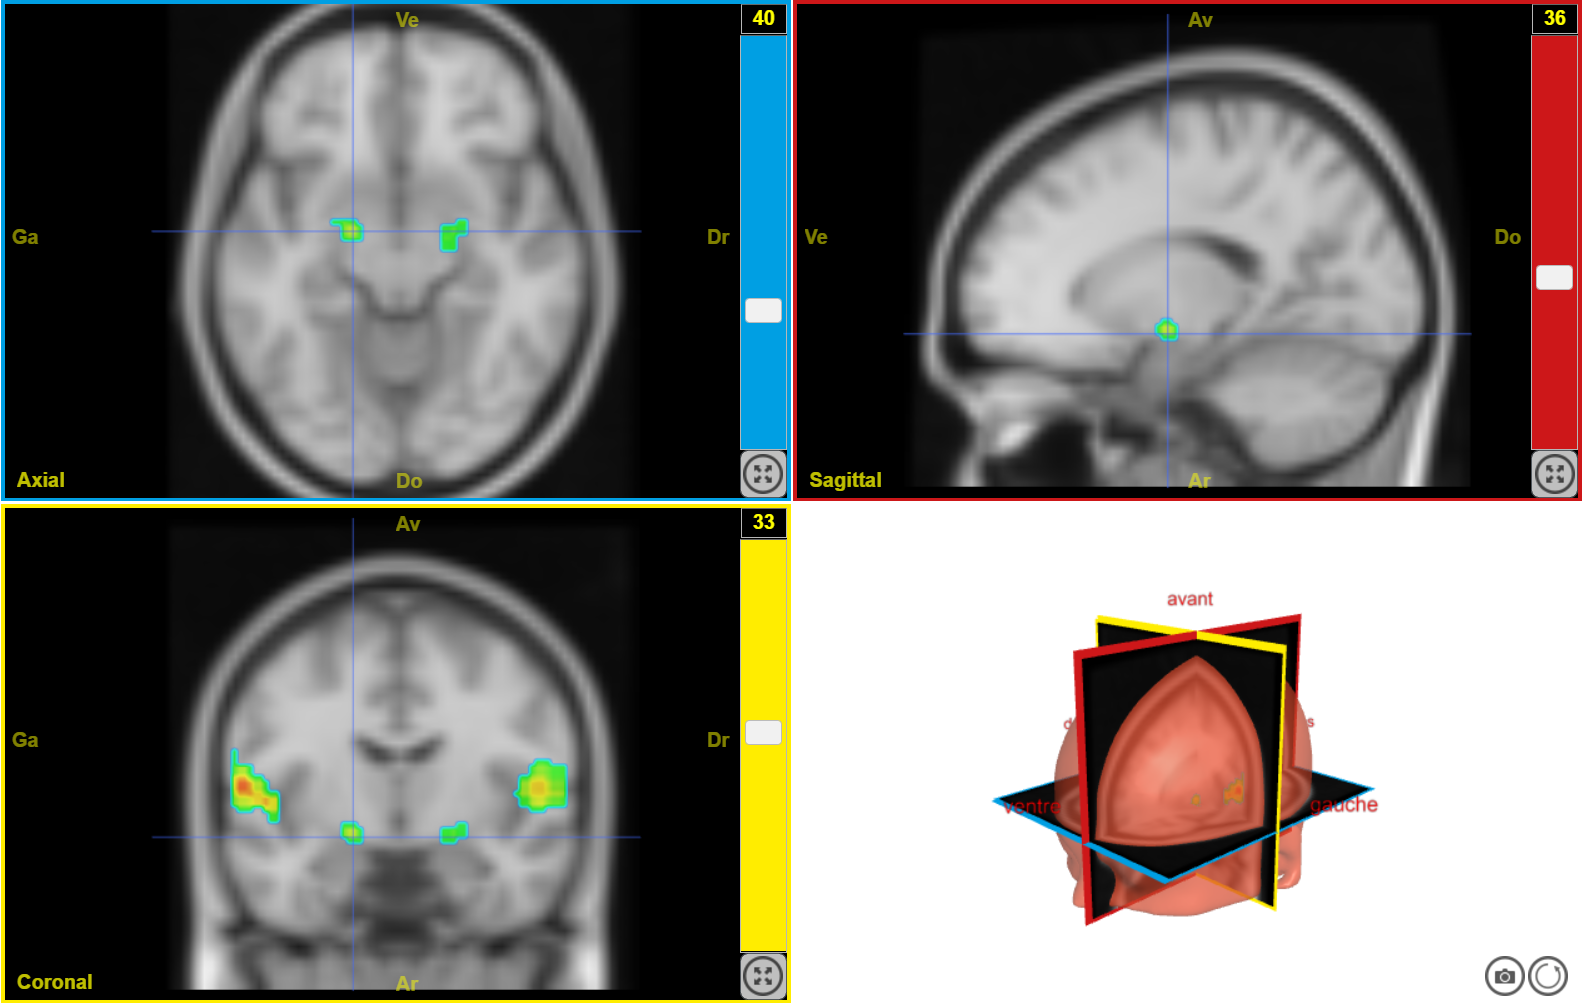

IRMf musique joyeuse 2